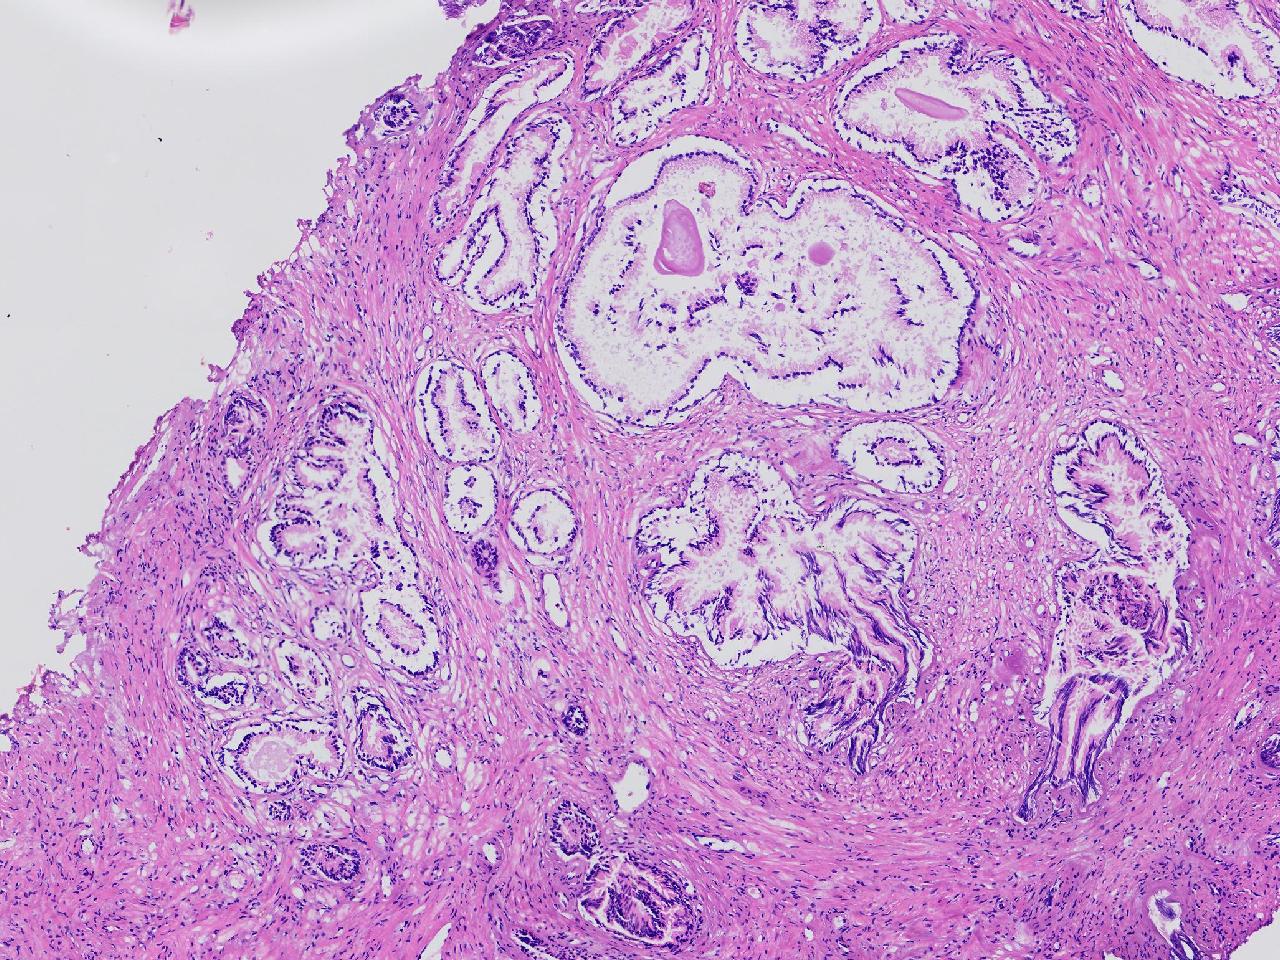

良性前列腺增生?

男,68岁,排尿困难半年余。行前列腺前切术。

前列腺电切标本

灰粉色条索状软组织多块,4X3X3厘米。

考虑为良性前列腺增生症

良性增生

BPH.